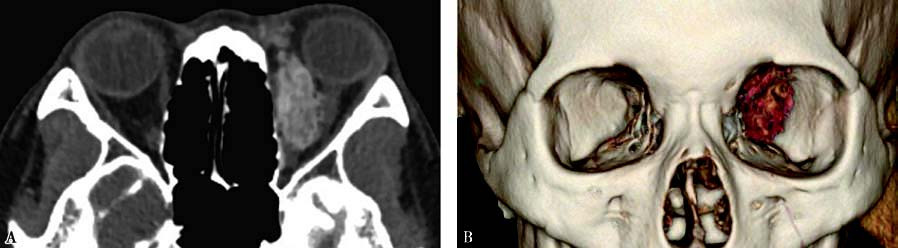

Figure 1 CT imaging of left orbital arteriovenous malformation

A. Contrast-enhanced CT image showing a poorly defined lesion with mixed density in the left orbit.

B. Three-dimensional reconstruction revealing an abnormal vascular mass along the medial orbital wall.

On CT imaging, orbital arteriovenous malformations often appear as poorly defined lesions with mixed-density signals, including hyperdense punctate or linear vascular structures. Some lesions may show hyperdense calcifications and hypodense areas of softening. Contrast-enhanced CT imaging often reveals worm-like enhanced clusters. MRI demonstrates the extent of the lesion and its anatomical relationships with great clarity. Both T1- and T2-weighted images exhibit characteristic flow voids, appearing as serpentine or globular low-signal areas within the lesion, surrounded by low signals from the feeding arteries and draining veins. Digital subtraction angiography (DSA) serves as the "gold standard" for diagnosing orbital arteriovenous malformations, providing detailed visualization of the feeding arteries, nidus, and draining veins.